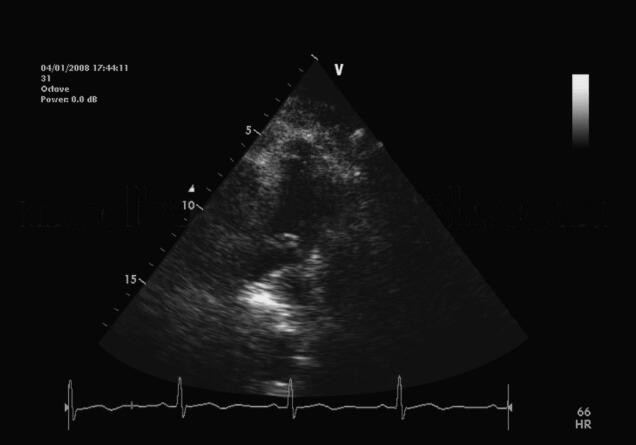

诊治经过:查双下肢静脉彩超示右下肢股浅静脉、静脉、胫腓干静脉、肌间静脉血栓。增强螺旋CT:左右肺动脉、右上下肺动脉及左上下肺动脉充盈缺损,考虑肺动脉栓塞,肺动脉高压可能。急诊经胸超声心动图示“右肺动脉近段内探及大小约5.0cm×1.3cm大小的中高回声团块,随血流飘动;肺动脉增宽,右心房、右心室扩大,估测肺动脉收缩压70mmHg”,见图2。即刻给予rt‐pA 50mg 静脉滴注溶栓治疗。溶栓结束后12小时复查经胸超声心动图,示右肺动脉近段内异常回声团块消失,估测肺动脉收缩压40mmHg。溶栓后予以普通肝素和华法林规范抗凝,住院20天后病情好转出院。

图2 超声心动图示右肺动脉近段内中高回声团块